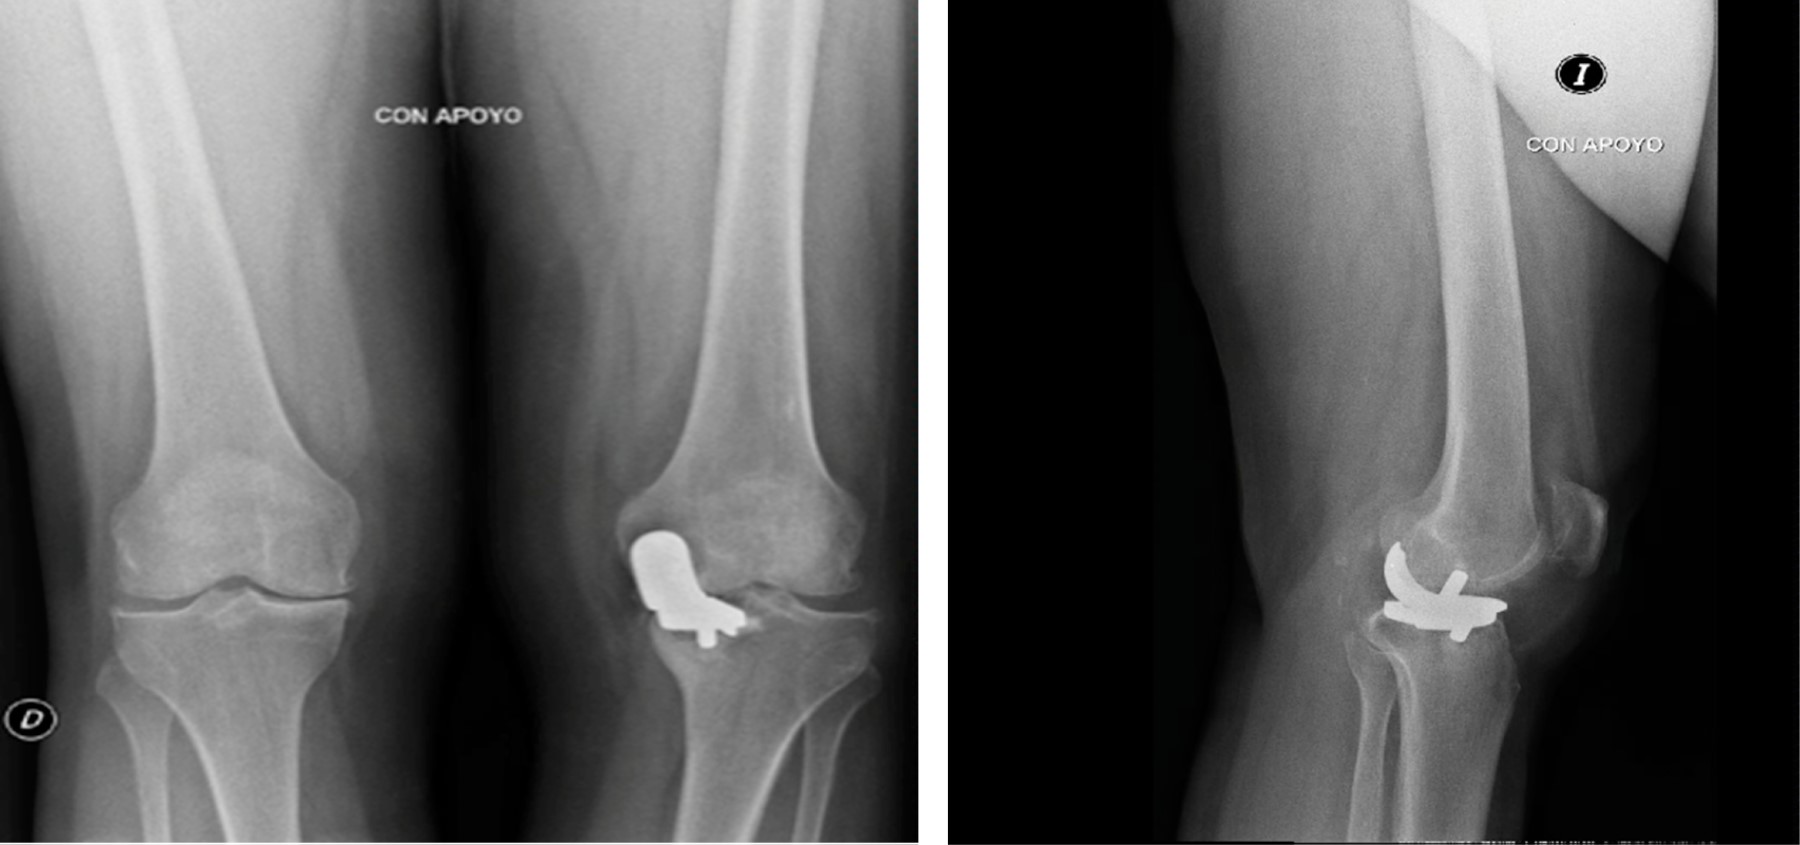

Figure 1

Figure 2